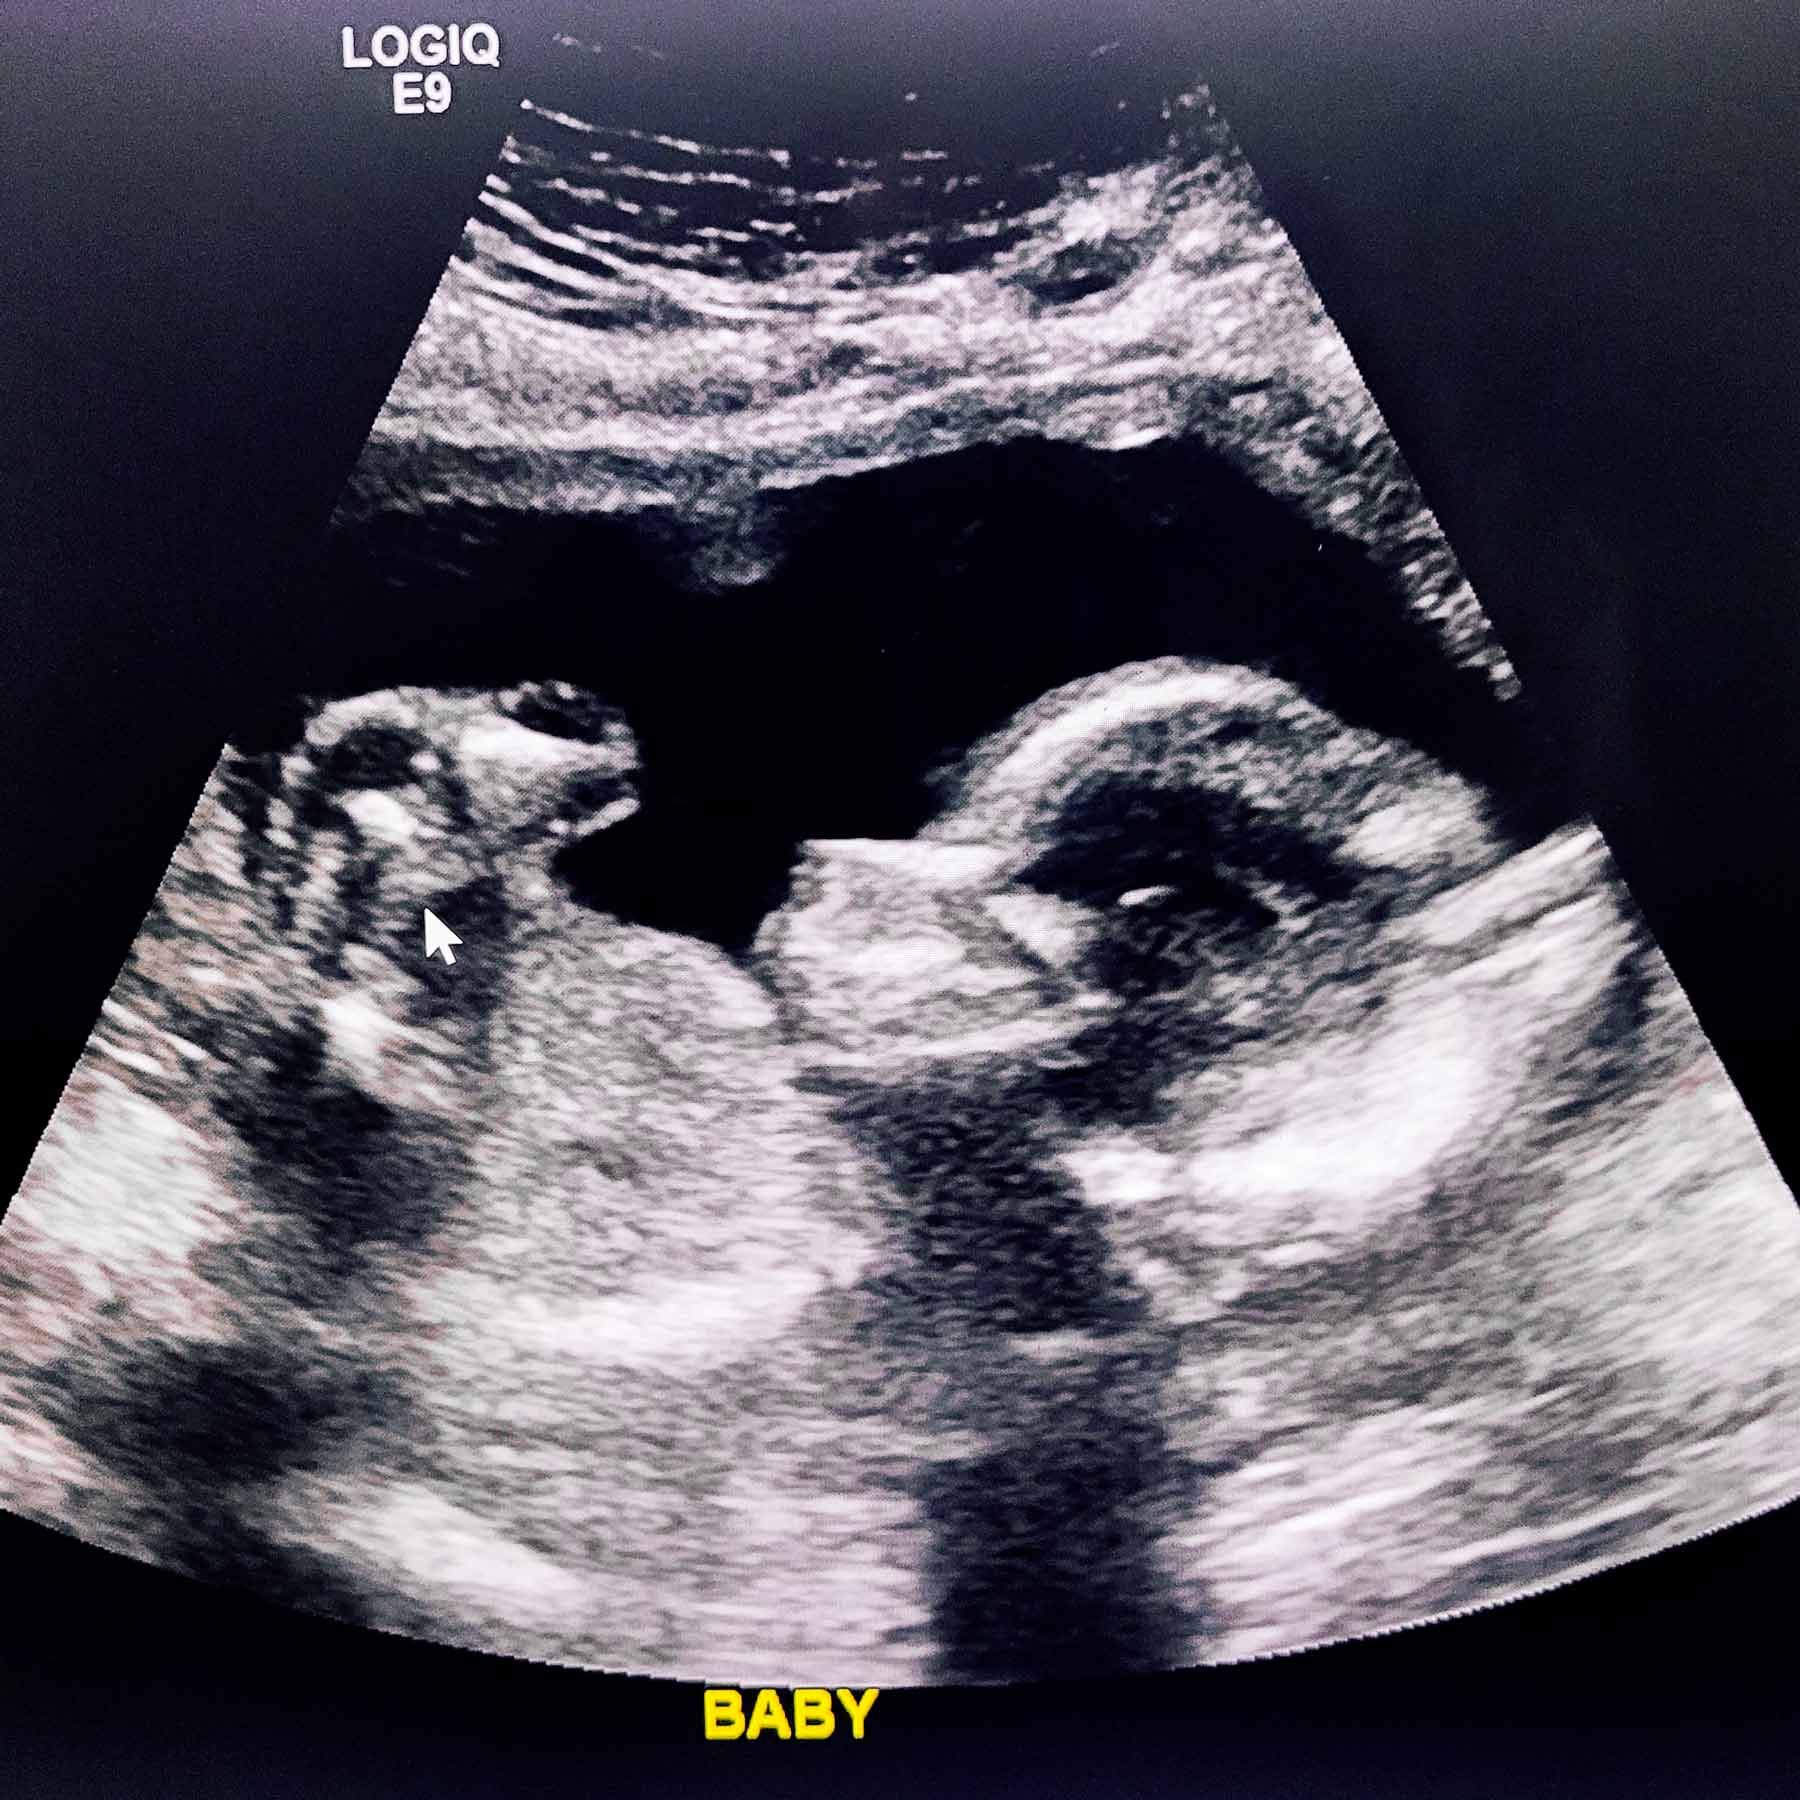

After 15 months of trying to get pregnant and partaking in every trick in the book, we finally purchased Mosie Baby, after a couple months of trying it finally worked. Although my first pregnancy ended in a tubal and miscarriage, I am now 23 weeks pregnant with our baby girl!